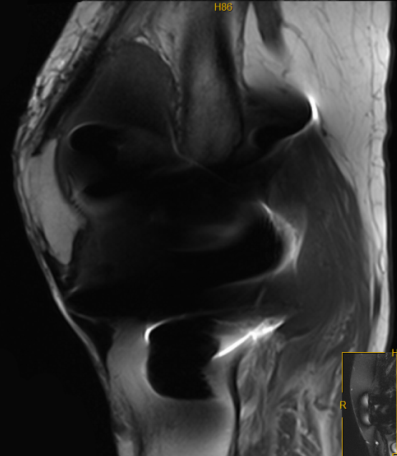

▲ MRI提示:滑膜组织增生,关节腔积液,囊肿形成